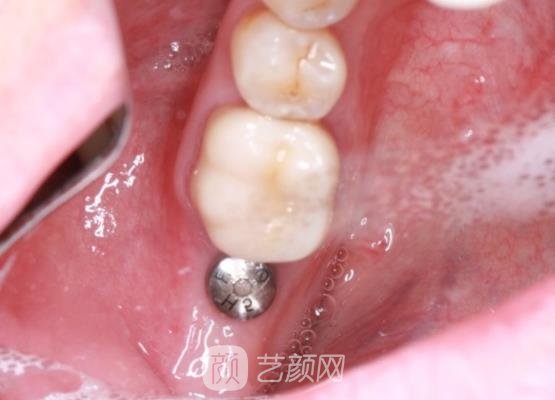

方案确定好之后手术就开始了,刚开始手术的时候我也是很紧张的,一直都是比较害怕的状态,不过医生的服务态度真的很好,还很耐心的安慰我,我紧张的情绪才缓解了很多,几个小时手术就完成了。

刚结束手术的时候,我的口腔里面还有着一些不适应的感觉,而且牙齿也很无力,医生随后对我的牙齿条件进行了相关的检查之后,然后又叮嘱了我一些术后的注意事项。